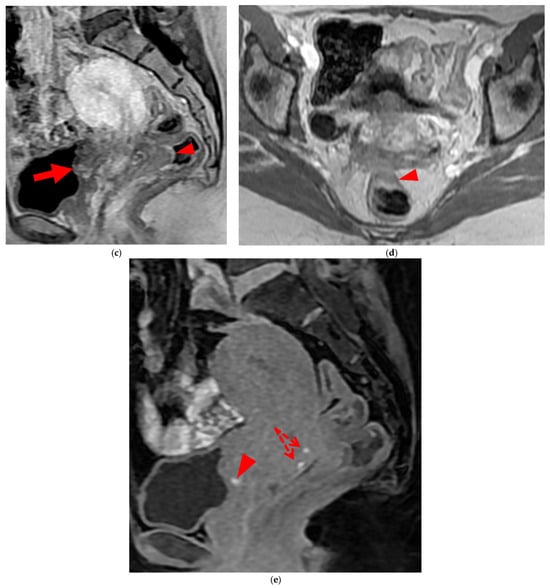

2.2.1. HTD Type 4 USL (PPV = 100%; FPR = 0%)

A type 4 USL (Figure 5) contains hemorrhagic implants, visible on MRI as hyperintense spots on fat-suppressed T1WI.

Figure 5. Pelvic MRI scans of two patients with HTD type 4 USLs. (a,b) Patient 1—(a) Axial T2WI: a focally thickened right proximal USL (arrowhead) with caliber disparity, initially classified as a type 3B USL. (b) Axial fat-suppressed T1WI: a hyperintense hemorrhagic spot (arrowhead) within this thickened right proximal USL, ultimately reclassifying it as a type 4 USL. Note the typical hyperintense right ovarian endometrioma (red star). (c,d) Patient 2—(c) Sagittal T2WI: a visible but thin (1.5 mm) left USL (arrowhead), initially classified as a type 2 USL. (d) Sagittal fat-suppressed T1WI: a hyperintense hemorrhagic spot (arrowhead) at the origin of this USL, ultimately reclassifying it as a type 4 USL.